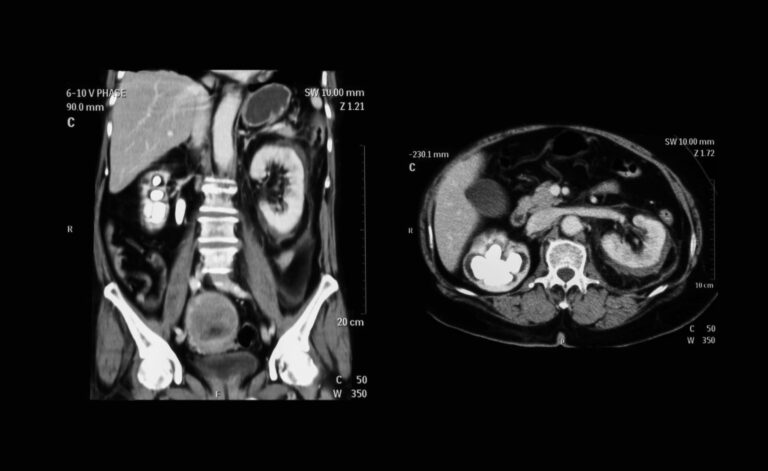

• CT Colonography (Virtual Colonoscopy) – A less invasive option using imaging technology.